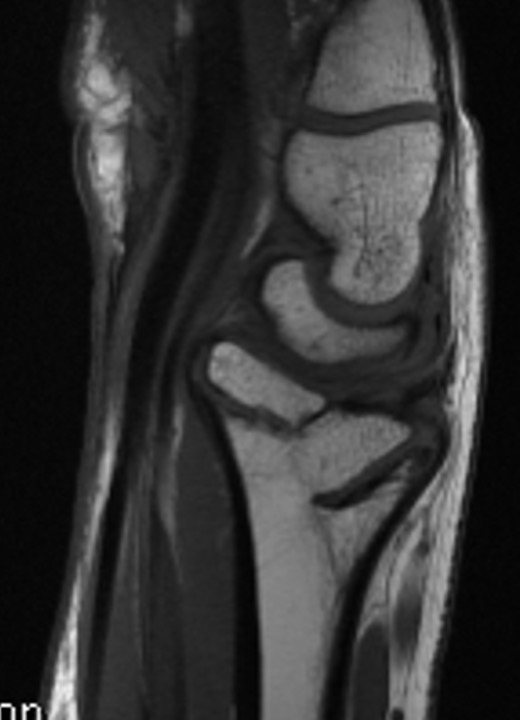

Xray

CT

MRI